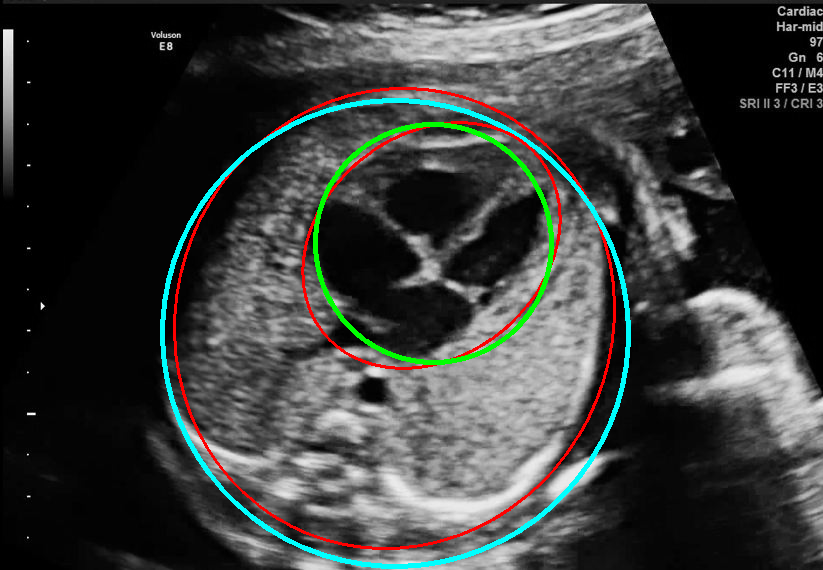

Results of ablation study.

As shown in Fig. 3 , both the proposed ellipse regression loss and IoU loss are necessary for ellipse detection. If the EllipseNet only supervised by IoU loss (first column), the model fails to optimize the major and minor axis separately, and the predicted ellipses degenerate into circles like the CircleNet. It is clear that the supervision of IoU loss can help to improve the prediction of location and shape (first and second row) and to correct the angle (last row).